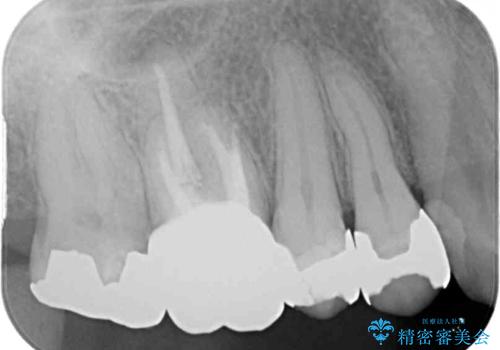

- 右上の小臼歯部に咬んだときに強い痛みを感じるとのことで来院された患者様です。

診査を行った結果、根管治療を行った後にオールセラミッククラウンにて補綴する治療計画となりました。

咬んだときの痛みに加えて夜間のズキズキする痛みもありましたが、1回目の根管治療実施後間もなく咬んだときの痛みがなくなったので、2回目に根管充填を行いました。